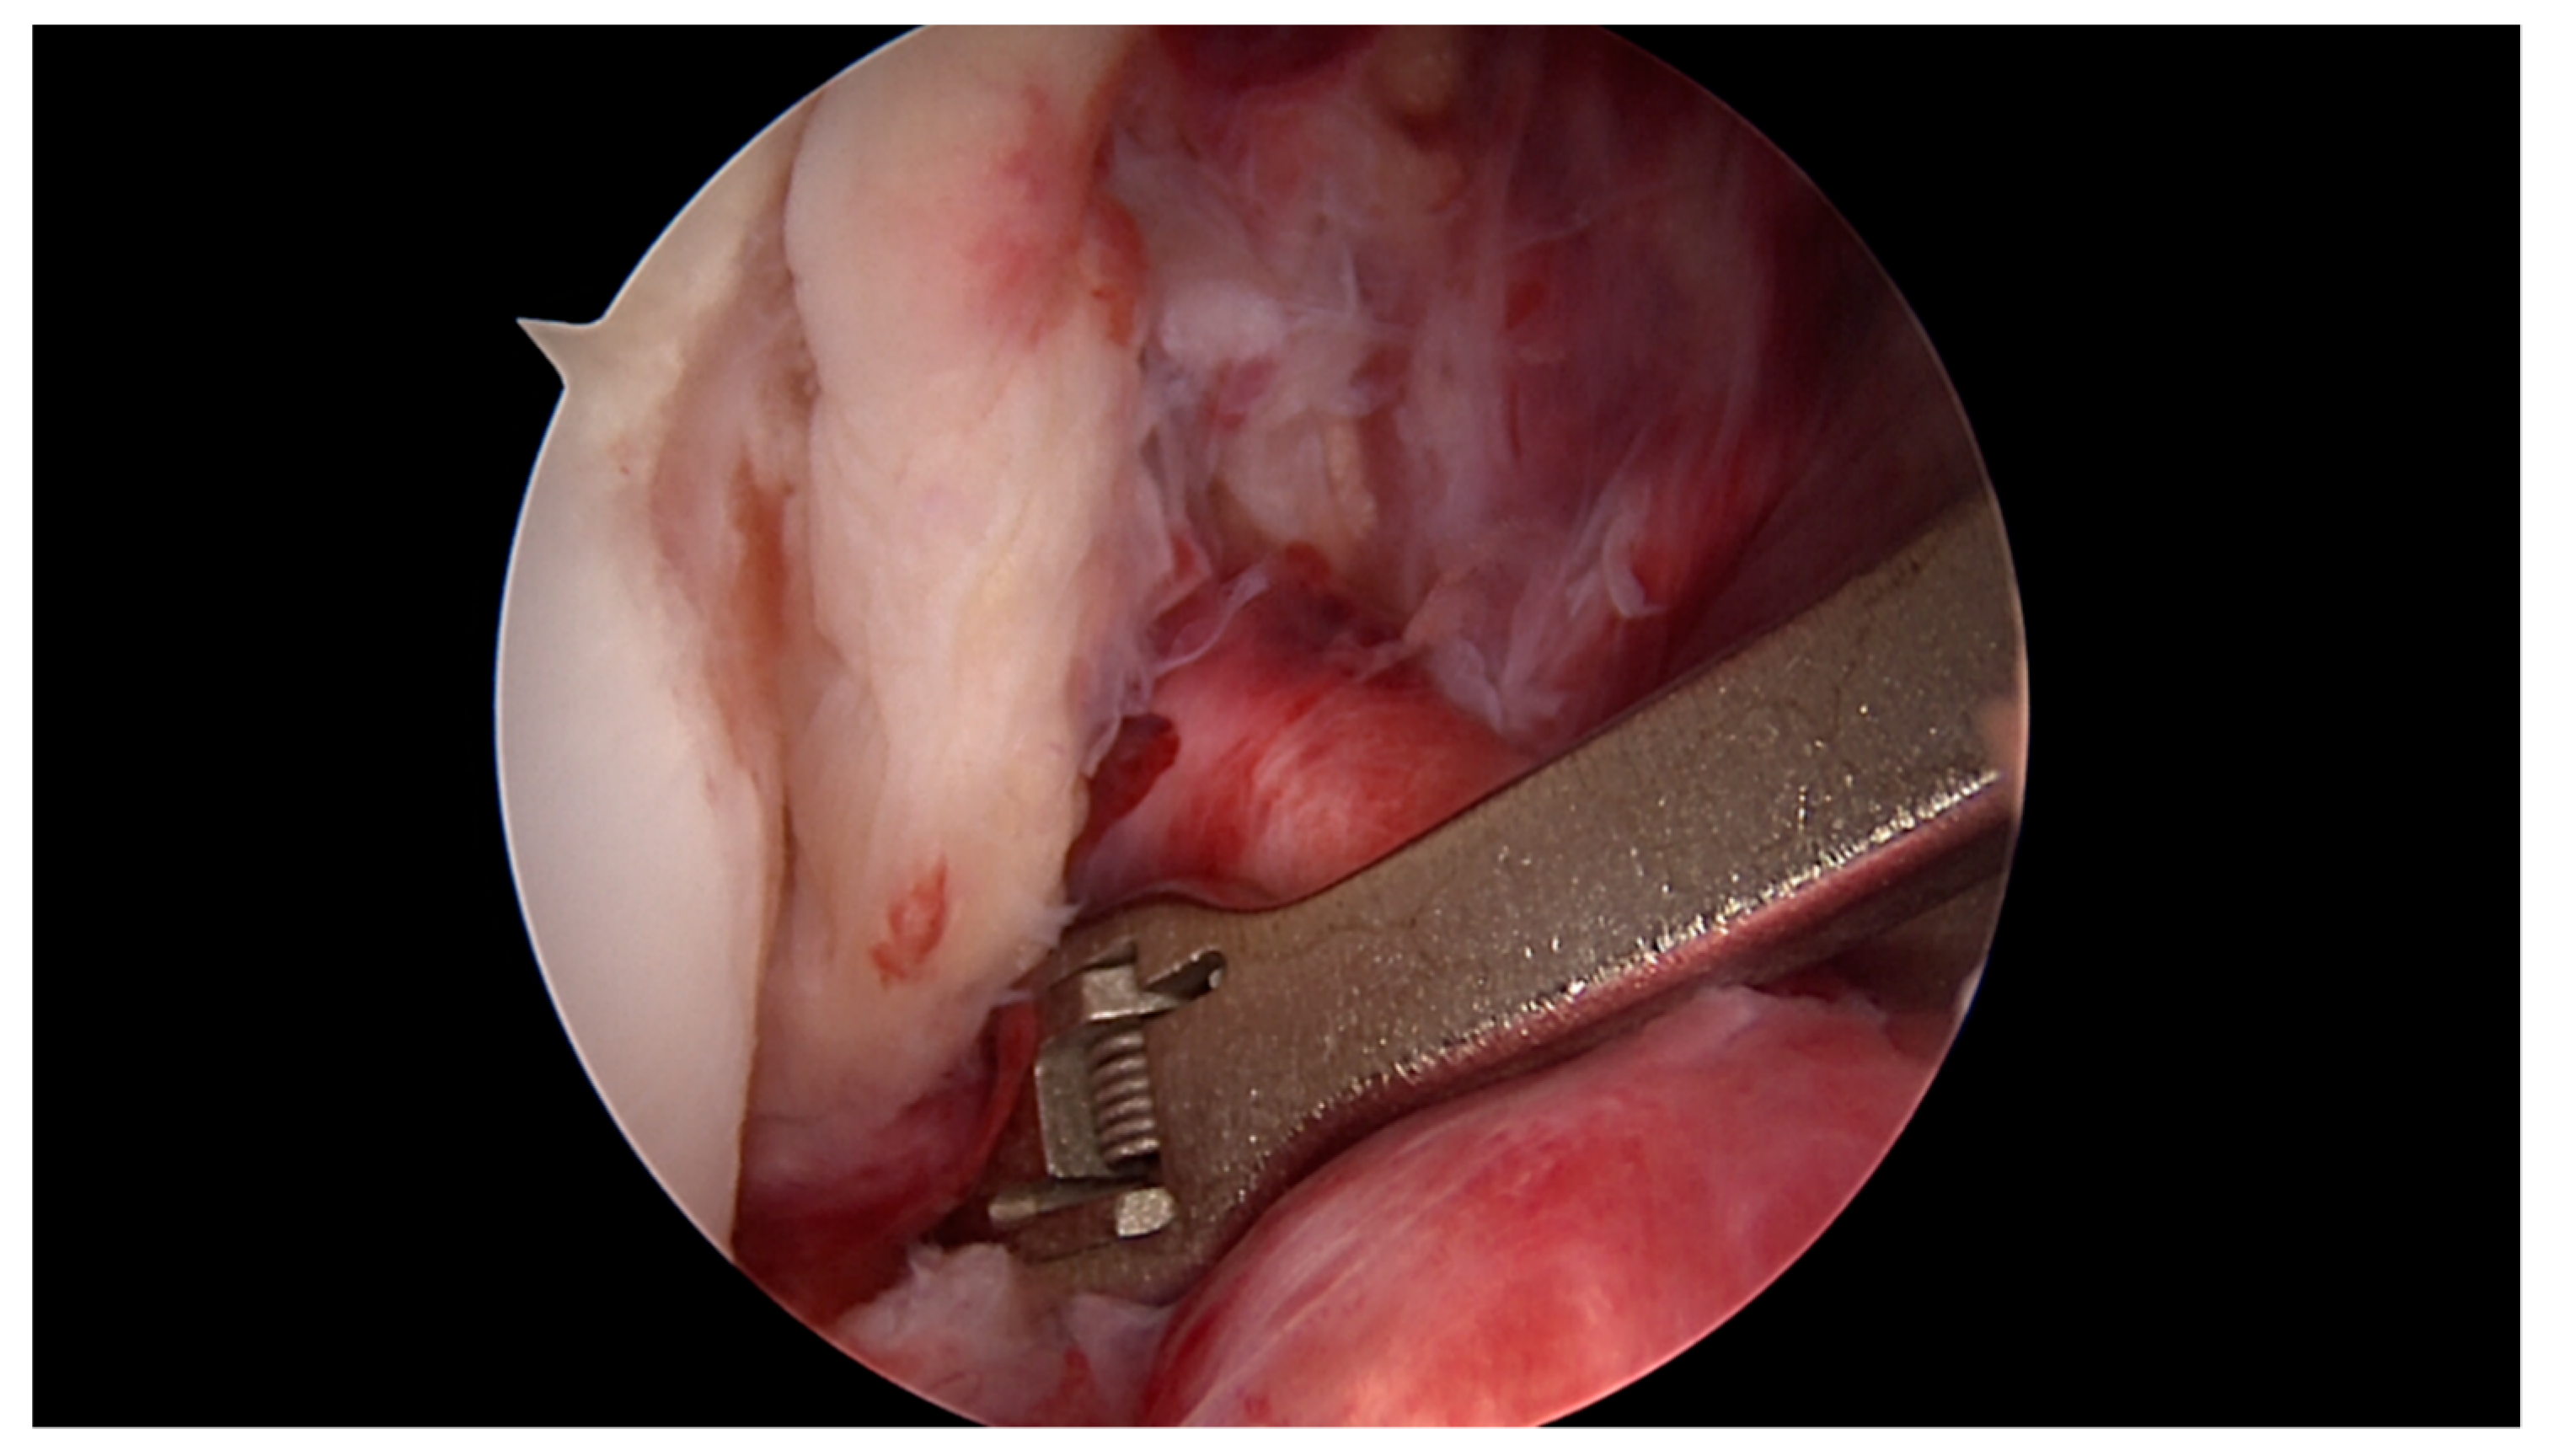

2.1. Surgical Technique and Rehabilitation